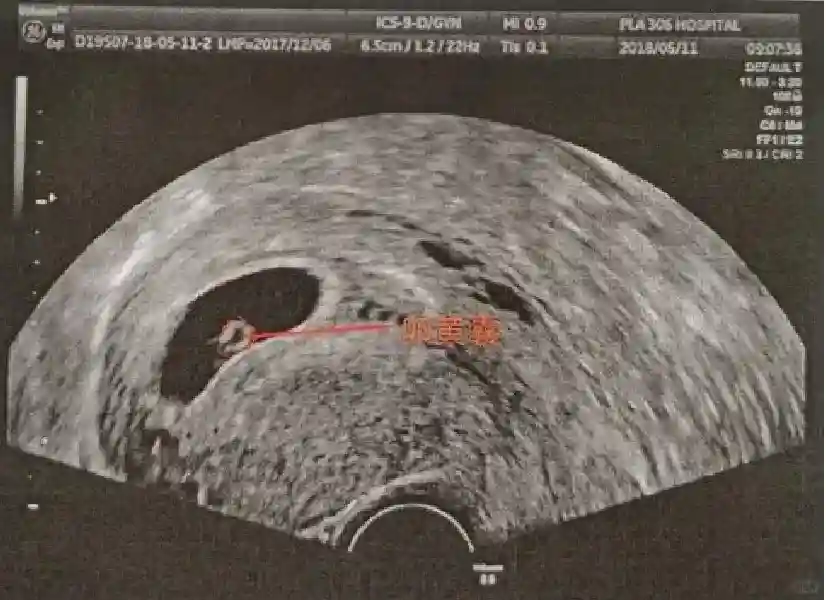

2??卵黄囊:是妊娠囊内第一个解剖结构,直径<7mm。表现为小环状,中央为无回声,囊壁薄,内透声好。卵黄囊位于胚胎旁胚外体腔内。卵黄囊通常在孕5-6周时出现,5-10周稳步增长,一般不超过7mm,至12周消失。妊娠囊的大小与卵黄囊之间有一定关系,妊娠囊平均直径> 8 mm 时,经阴道超声均应显示卵黄囊,妊娠囊平均直径> 18 mm 时,经腹超声均应显示卵黄囊。